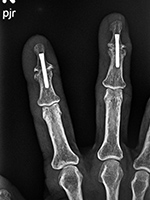

| Accutrak screws

|

| The Accutrak screws are used for arthrodesis of the distal interphalangeal joints of the right index and long fingers in a woman with severe osteoarthritis.